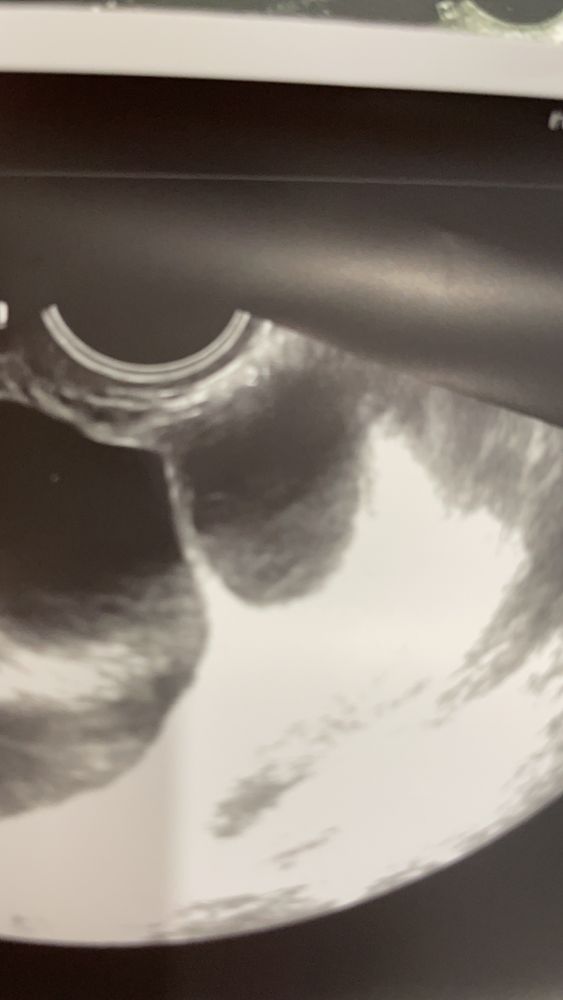

Ирина, я буду рада любому исходу событий 😂я уже жду месячных как никогда, потому что мечтаю, чтобы они быстрее рассосались , чтобы нормально заниматься спортом!но эти узисты и врачи говорят, что даже Б исключить нельзя, и даже врач сказала, что это похоже на ЖТ…. Вблизи на фото чуть другая структура там

Ирина, подскажите, даже приближённее не похоже на ЖТ

Ксюша, как по мне - они идентичны у вас на фото и это оба фолликулы, фолликул на узи имеет чёткие границы и внутри как бы чёрное пространство. 5 лет стажа планирования и моя любимая узистка мне показывала и рассказывала как и что)) у меня качество не такое хорошее, но вот на одном фото фолликул 13 мм и жёлтое тело 17мм, жёлтое тело совсем другой консистенции